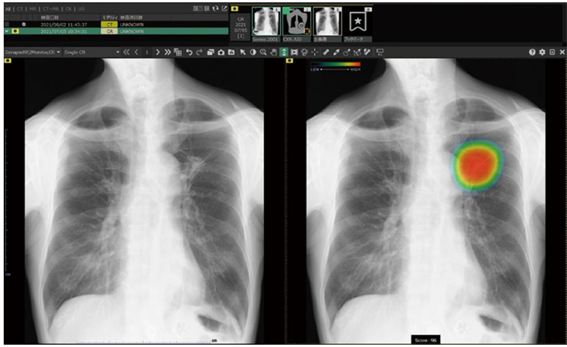

胸部(肺)のレントゲン画像内の腫瘤や気胸等の病気を検出し、見落とし防止を支援するAI技術を活用したシステムです。

撮影した胸部単純X線画像を自動解析。結節・腫瘤影、浸潤影、気胸が疑われる領域を検出しマーキング。その領域を医師が再確認することで、見落し防止を支援します。